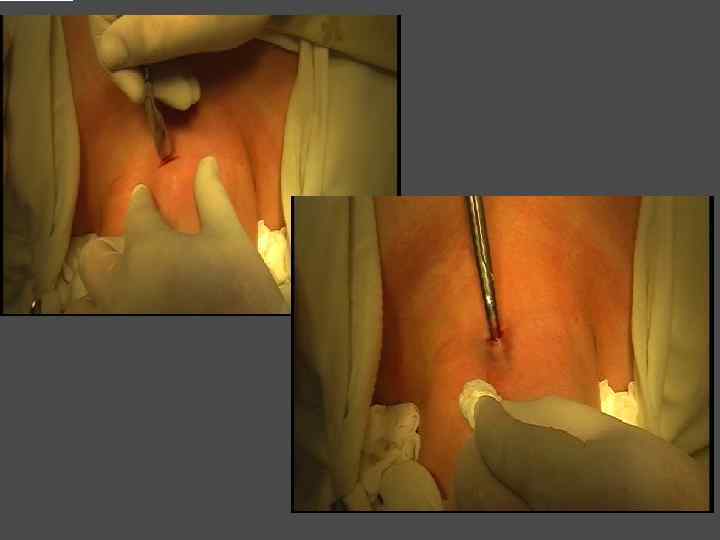

ЧРЕСКОЖНАЯ СКЛЕРОЗИРУЮЩАЯ ТЕРАПИЯ ЭТАНОЛОМ

ПОКАЗАНИЯ I. Показания, те же, что и к хирургическому лечению + ► Сопутствующая патология, исключающая возможность хирургического лечения. ► Категорический отказ больного от хирургического лечения. II. Солитарный (единичный) узел небольшого размера (<3 см)

ОБЯЗАТЕЛЬНОЕ УСЛОВИЕ ► Доброкачественный характер узлового образования Всем больным проводится пункционная тонкоигольная аспирационная биопсия под контролем УЗИ

ЭТАПЫ ЭТАНОЛОВОЙ ДЕСТРУКЦИИ УЗЛА БОЛЬШОГО ОБЪЕМА